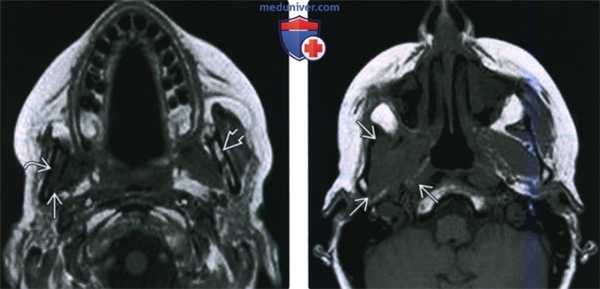

(Слева) МРТ Т1ВИ в аксиальной проекции, пациент, которому ранее проводилось лечение по поводу плоскоклеточного рака носоглотки. Костный мозг в правой ветви нижней челюсти замещен опухолевой тканью, на уровне отверстия нижней челюсти также определяется патологическая ткань, появление которой связано с распространением опухоли по нижнечелюстному нерву. Обратите внимание на нормальный костный мозг левой ветви нижней челюсти, который имеет гиперинтенсивный сигнал.

(Справа) МРТ Т1ВИ в аксиальной проекции, этот же пациент. Периневральное распространение опухоли по нижнечелюстному нерву с облитерацией жировой клетчатки жевательного пространства.